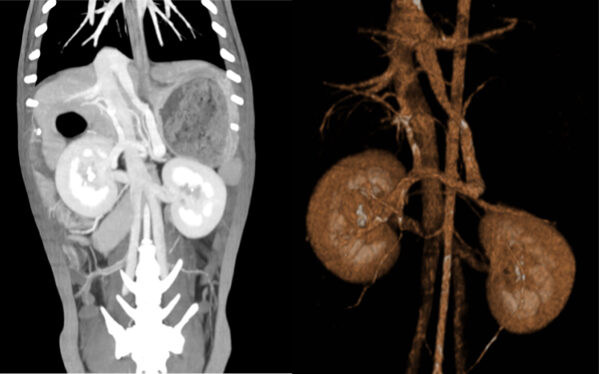

혈관·장기 3D 확인

혈관과 장기 구조를 함께 확인해 수술·치료 계획에 도움됩니다.

(참고사진 : 혈관 이상 또는 종양 평가가 필요한 환자의 3D CT 영상)